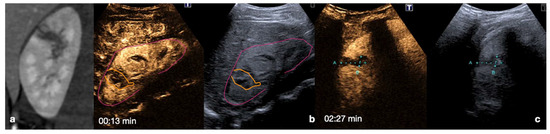

Figure 24.

An example of multimodal visualization of post-traumatic splenic PSA (white arrows) at CD–US (a), CEUS (b), and arterial phase contrast-enhanced CT scan (c); CEUS follow-up examination after embolization (d) showed no evidence of residual PSA.

Figure 25.

Splenic trauma in car accident with small splenic laceration visible on contrast-enhanced CT scan performed at emergency department (a,b, white arrowhead). CEUS examination performed 4 days after trauma confirmed the splenic laceration (c, white arrowhead); subsequent Flash mode CEUS (d) revealed multiple, small and diffuse intra-splenic PSAs (white arrows) not shown at admission arterial phase CT exam (a); these findings were confirmed at contrast enhanced CT scan (e, arrows) and angiography (f, arrows).